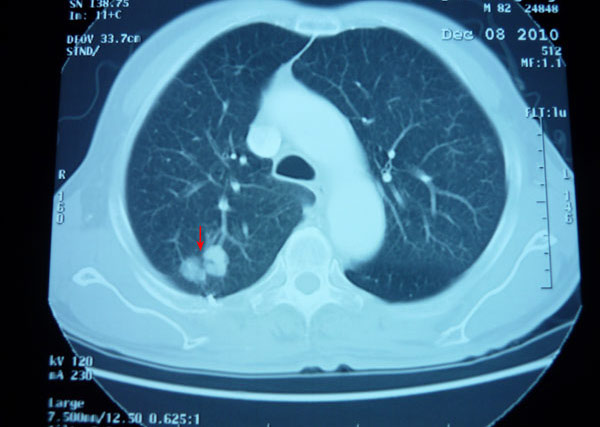

一位86岁罹患肺癌的高龄老人,经广西中医药大学附属瑞康医院射波刀治疗6天后出院,1年后复查肿块消失,2年后复查肿瘤无复发。 2010年 7月,...